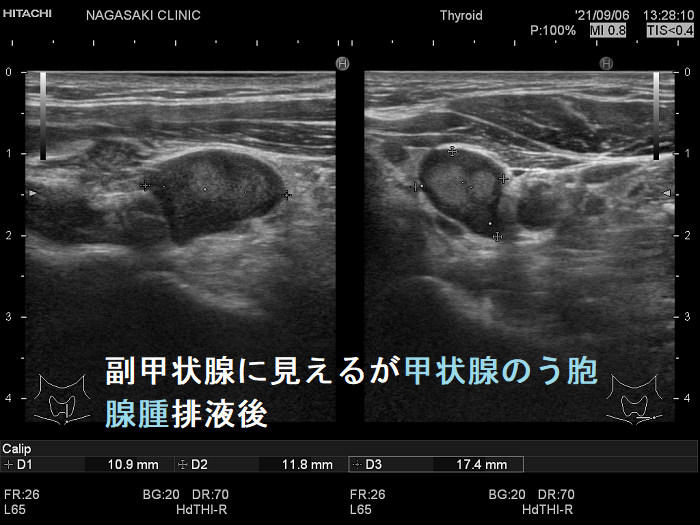

副甲状腺腺腫のように見えるも、実は排液後の甲状腺のう胞腺腫(甲状腺嚢胞腺腫)

副甲状腺腺腫と同じような位置(写真では甲状腺左葉の下極)にあり、副甲状腺腺腫のように見えるも、実は排液後縮小した甲状腺のう胞腺腫(甲状腺嚢胞腺腫)です。

最初から、その場所に甲状腺のう胞腺腫(甲状腺嚢胞腺腫)があったことを知っていれば何の問題も無いのですが。

下の写真を見て分かる通り、副甲状腺腺腫と鑑別が付きません。

副甲状腺に見えるが排液後縮小した甲状腺のう胞腺腫(甲状腺嚢胞腺腫) 超音波(エコー)画像

副甲状腺に見えるが排液後縮小した甲状腺のう胞腺腫(甲状腺嚢胞腺腫) 超音波(エコー)画像 ドプラーモード